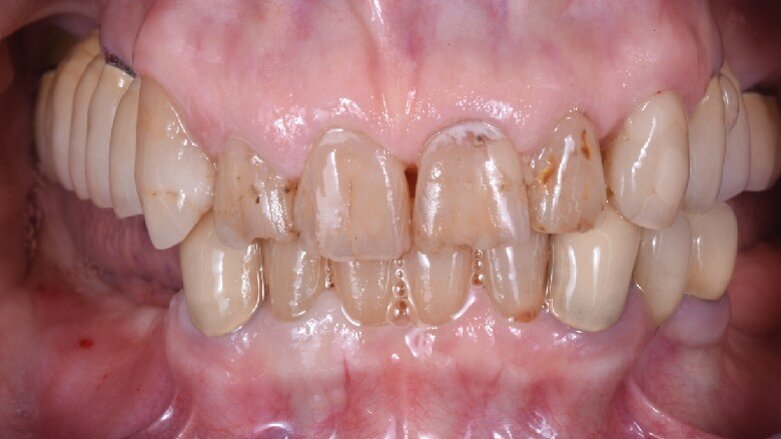

Una paziente di 65 anni si presentò alla nostra attenzione, riferita dal dentista curante, per risolvere il suo edentulismo posteriore bilaterale. L’anamnesi medica era negativa, mentre la paziente riferiva di aver perduto i denti diatorici come conseguenza di fratture susseguenti ad una vecchia protesizzazione (Fig. 1a).

Circa otto settimane più tardi si è potuto notare l’integrazione degli innesti (osseo e tessuto molle) e la notevole differenza nel volume vestibolare della cresta (Fig. 13). Tre mesi dopo la scopertura degli impianti e dopo che i tessuti erano completamente guariti venivano rilevate le impronte e finalizzate le corone in zirconia (Fig. 14). La rx rilevata a sei mesi dalla finalizzazione protesica (Fig. 15) dimostra la stabilità del complesso implanto protesico e la completa ricostruzione del difetto osseo circostante agli impianti.

Fig. 14 - Le corone definitive in posizione.